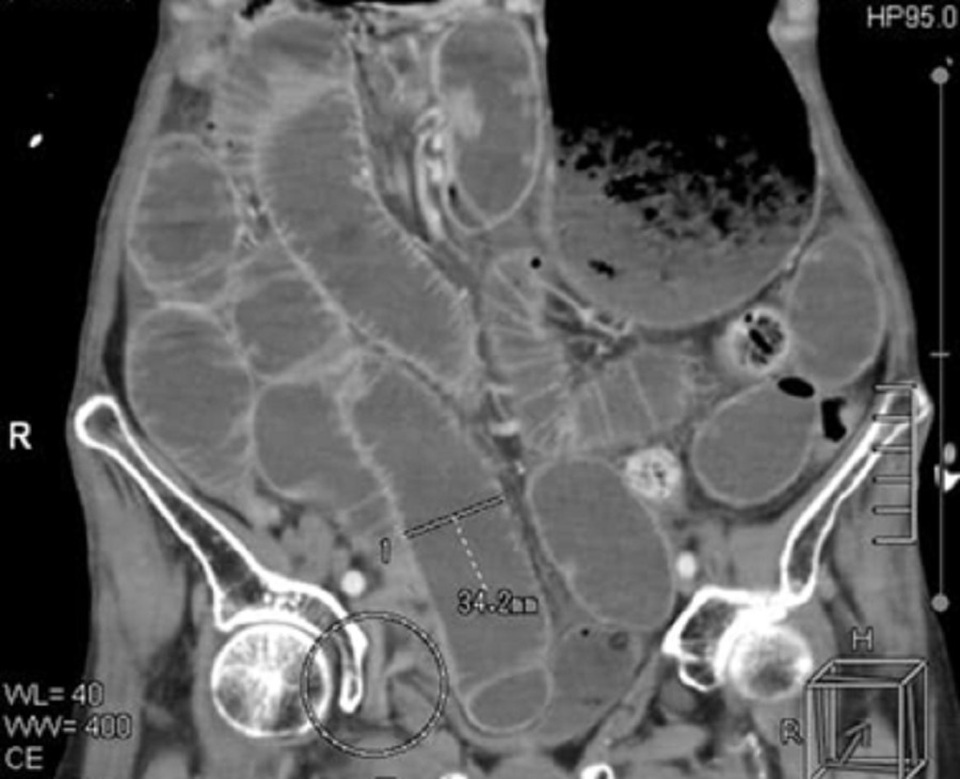

Hình ảnh kiểm tra cho người bệnh, bác sí phát hiện ruột non chui vào lỗ bịt

Qua thăm khám, chẩn đoán hình ảnh, bác sĩ phát hiện bệnh nhân bị tắc ruột, nhiễm trùng nặng trên nền bệnh tim và bệnh thận mạn tính. Truy tìm nguyên nhân gây ra tình trạng trên ở người bệnh, bác sĩ ghi nhận hình ảnh phim CT có 1 quai ruột non chui vào lỗ bịt dẫn tới tắc ruột và hoại tử ruột.